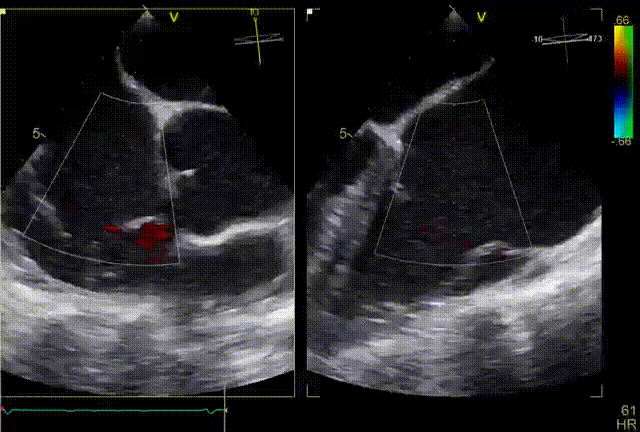

术前超声

术后超声